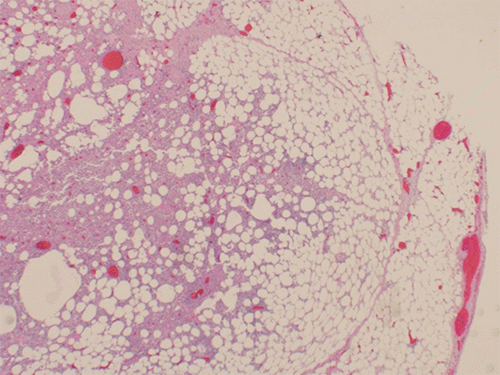

The patient underwent exploratory laparotomy, sigmoidectomy, creation of a Hartmann pouch, and end sigmoid colostomy on hospital day 6. Intraoperative findings included phlebitis of the entire length of the IMV extending from near the ligament of Treitz to the superior hemorrhoidal veins. There was retroperitoneal inflammation extending down to the true pelvis. The surgical pathology report showed a benign sigmoid colon with diverticula, subserosal acute and chronic inflammation, abscess formation, fat necrosis, and endovascular thrombi (Figure 2).

Figure 2. Hematoxylin- and Eosin-Stained Pathology Slides, A) Inferior Mesenteric Vein Thrombus and B) Subserositis. Published with Permission

A) Inferior Mesenteric Vein Thrombus

B) Subserositis